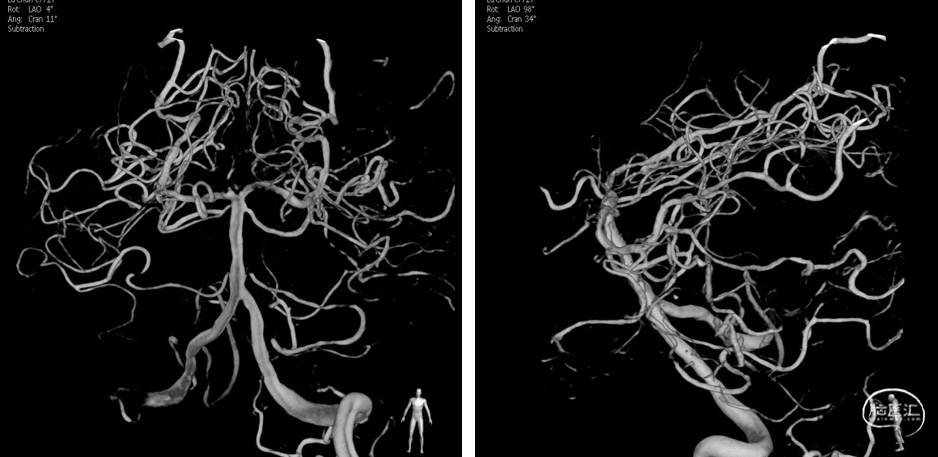

左侧椎动脉造影见基底动脉尖动脉瘤,大小约4mm x 4mm,瘤颈约3.5mm。

经双SL-10微管于动脉瘤内交替填入弹簧圈:首先经直头SL-10微导管于动脉瘤内输送Jasper®SS 4mm x 10mm弹簧圈,输送一半后,经45度SL-10微导管于动脉瘤内输送Jasper®SS 3mm x 10mm弹簧圈,缠绕第一枚弹簧圈,使其稳定,继续填塞第一枚弹簧圈随后解脱,继续填塞第二枚弹簧圈随后解脱,两枚弹簧圈相互缠绕填塞后,在动脉瘤内稳定,继续经直头SL-10微导管于动脉瘤内填入Jasper®SS 3mm x 6cm弹簧圈随后解脱,然后经45度SL-10微导管于动脉瘤颈部输送Jasper®SS 2mm x 4mm 弹簧圈随后解脱,最后经直头SL-10微导管于动脉瘤颈部填入Jasper®SS 1.5mm x 2cm弹簧圈后解脱,造影见动脉瘤不显影,双侧大脑后动脉显影良好,动脉瘤得到Raymond 1级致密栓塞。